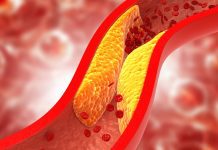

Atherosclerosis can be cured if it is spotted in early in life

An international research team has found that elevated lipids and dyslipidaemia in early life may worsen cases of atherosclerosis in later life.

The study found...